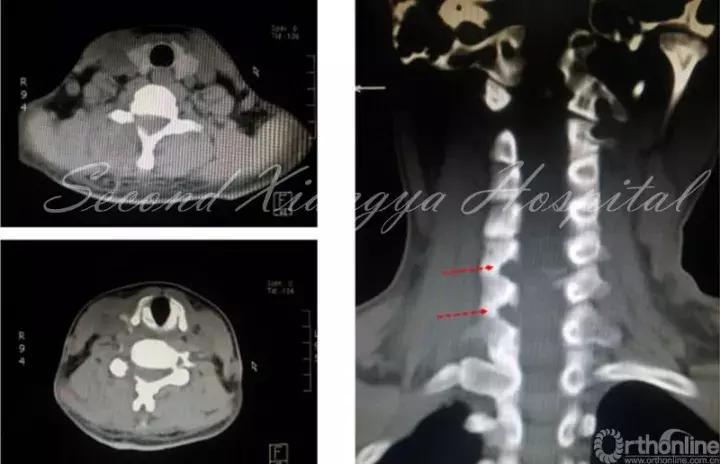

经皮内窥镜在颈椎中的应用,有后路经椎间孔入路,前路经椎间隙和椎体两种入路。后路经椎间孔入路的适用范围主要包括C3-7神经根型颈椎病、颈椎间孔骨性狭窄,亦有部分颈椎管局限性狭窄患者可以采取后路内镜下椎管减压的手术方式。前路经椎间隙适合中央型髓核突出,经椎体用于髓核脱垂类型,不适合颈椎不稳、成角、钙化、间隙高度<4mm和严重压迫者。

颈椎前路:

与颈椎后路相比,前路由于入路复杂、毗邻结构重要和颈椎解剖限制,通过前路进行髓核摘除有较大争议。对于平间隙水平的突出,可以通过经椎间隙或椎间孔进行减压操作,对于移位到椎体后缘者,可以考虑经椎体进行,但操作难度较大。颈椎前路经皮内镜手术高的围手术期并发症,以及远期疗效问题,仍然需要我们对这一入路,通过循证医学角度,来科学看待,客观分析。